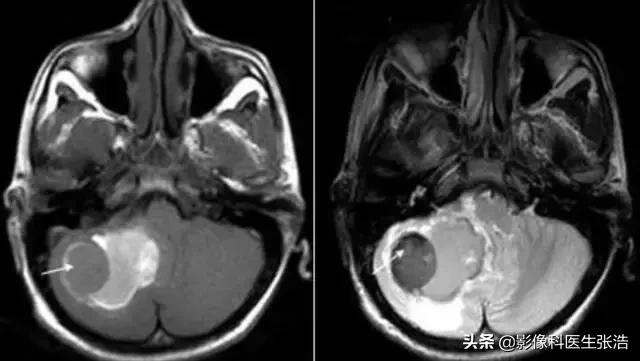

(3)肿 瘤:

MR图像上信号特征与肿瘤的组织结构类型相关。

例如:含脂类肿瘤,像脂肪瘤、胆脂瘤、畸胎瘤等呈短T1和长T2高信号特征;钙化和骨化性肿瘤呈长T1和短T2的低信号肿块;含顺磁性物质的肿瘤,如:黑色素瘤则呈短T1和短T2的信号特征;

而一般性肿瘤多数呈长T1和长T2的信号特征。富血管性肿瘤肿块内及附近可见扭曲扩张的流空血管影。